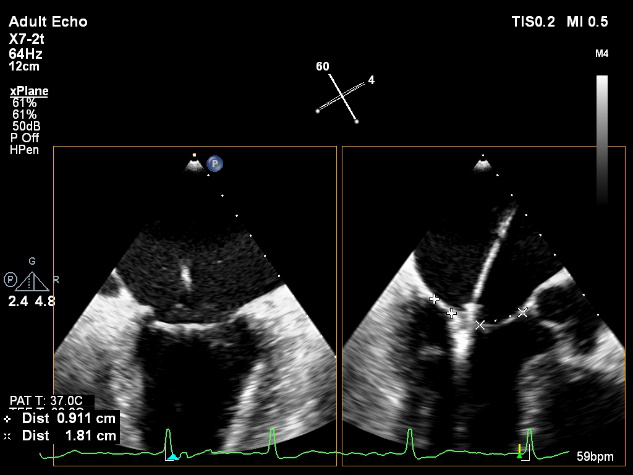

X-plane:下第夹子尝试捕获2区

X-plane:测量前叶长25mm,后叶长14.2mm

X-plane:计算前叶捕获长度8mm,后叶捕获长度7mm